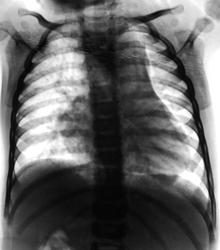

1 год и 4 месяца.

Размеры и форма сердечной тени "годятся" для врожденного порока, но ЭХО-кардиография обладает гораздо большими возможностями в этих вопросах, чем обзорная рентгенография.